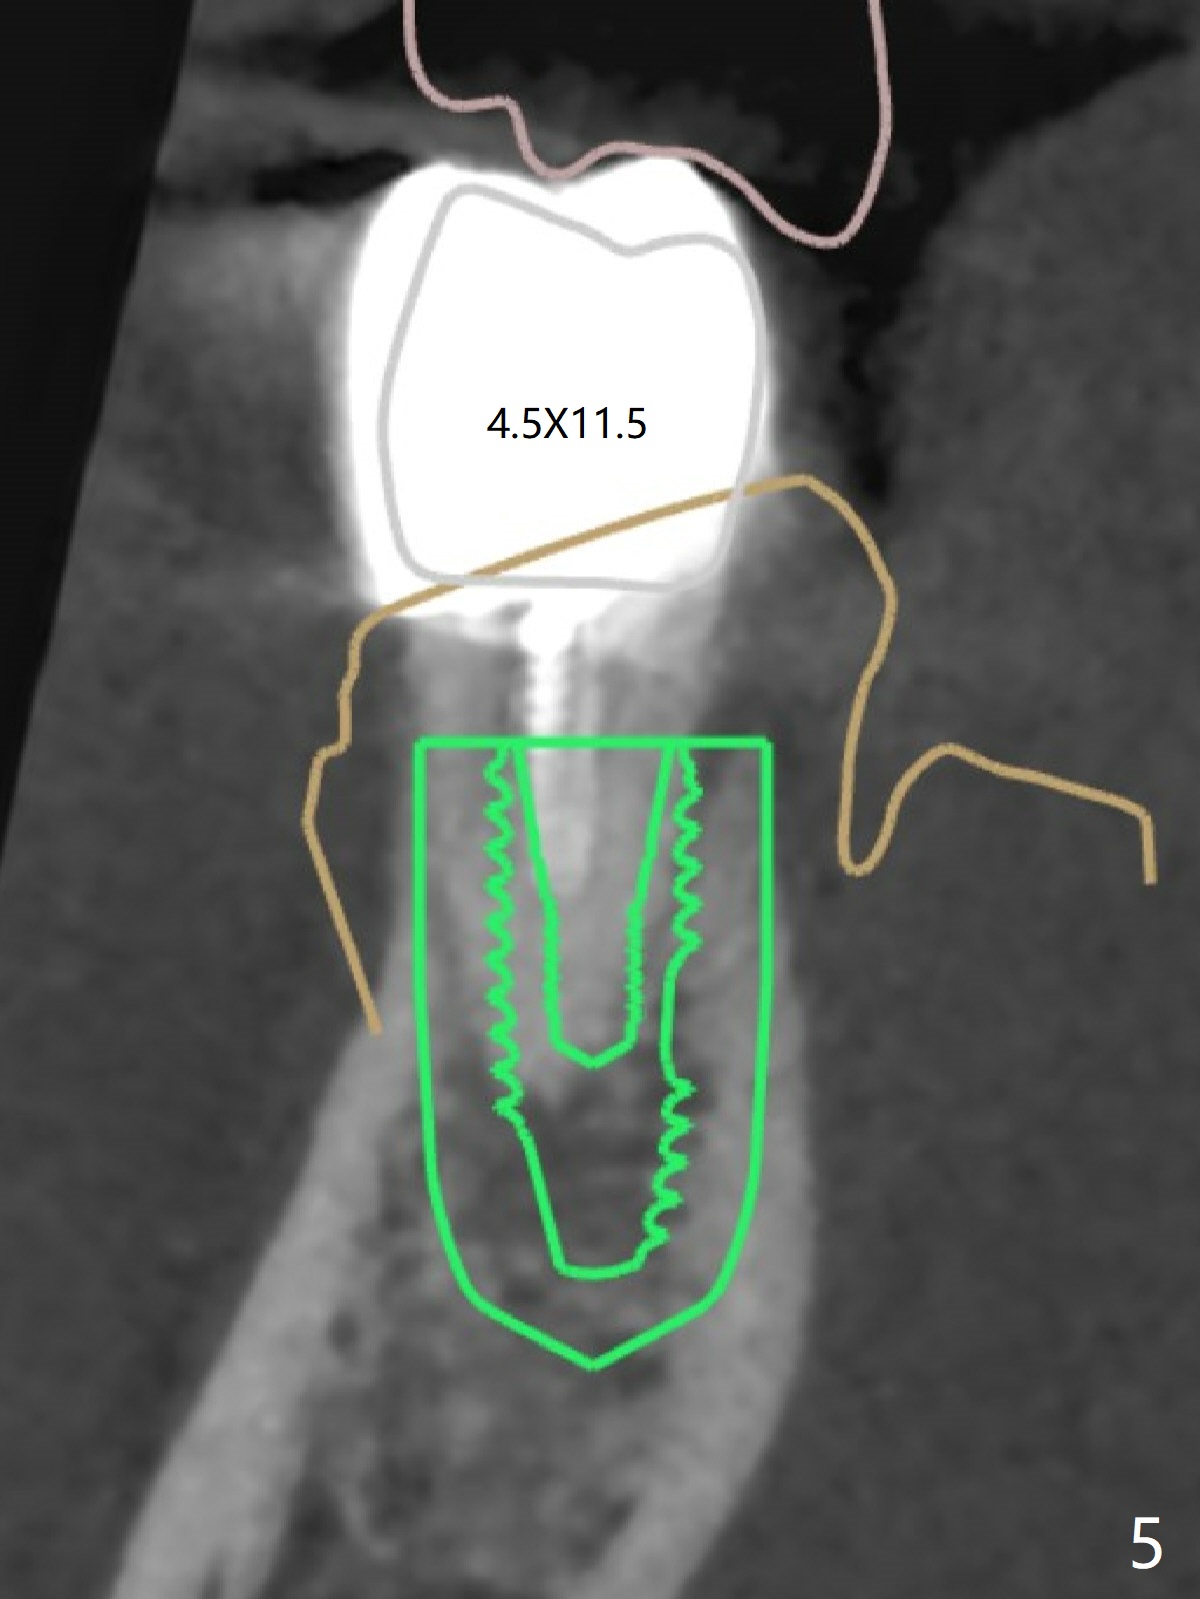

A 42-year-old man has been our patient for 3-4 years (Fig.1). An asymptomatic fistula develops lingual to the tooth #21 (Fig.2). An oblique fracture line appears to be next to a post (Fig.3 ^). A 3.5x11.5 mm implant seems to be able to be placed immediately lingual to the thick lingual plate with guide (Fig.4 L). No buccal deviation will occur with sufficient buccal gap. Design of an immediate implant at #21 (coronal section, Fig.5). In fact the root remains in place first (i.e., extract the crown first, Fig.5'). When osteotomy is done with the last drill 4x11.5 mm, there will be no deviation because of even counteraction between the buccal root and the lingual plate (Fig.6'). Then the root will be removed. But the 4.5x11.5 mm implant may be deviated buccal because of implant engagement into the lingual plate without buccal counteraction. Therefore, a 4x13 mm implant will be placed following 3.5x13 mm (last) drill. The implant is placed between the mesial and distal walls (Fig.7 sagittal section).